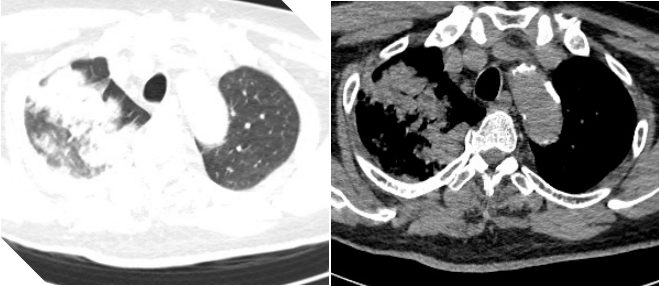

4月29日复查胸部CT如图2所示。

2 复查胸部CT2025-04-29)